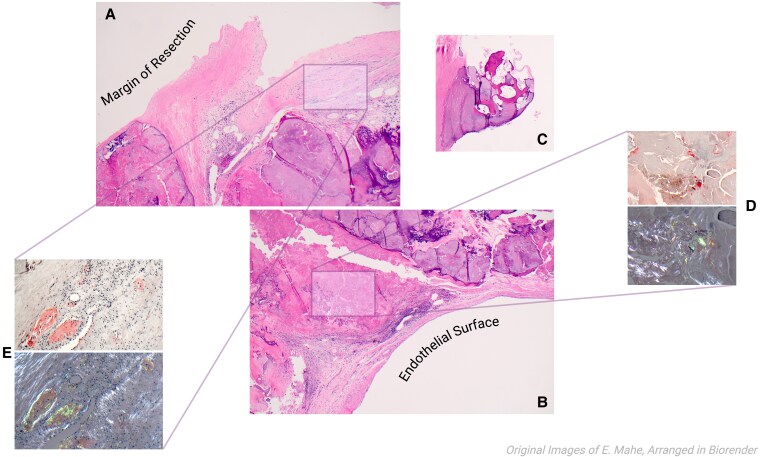

Case summary: We present a case of degenerative AS where the pathology analysis post-surgical replacement demonstrated amyloid deposits subsequently identified as AL subtype by mass spectrometry. Subsequent investigations demonstrated no myocardial or systemic involvement. Following multidisciplinary discussion, cardiac biopsy and chemotherapy were deferred given the isolated nature of aortic valve involvement and clinical stability.